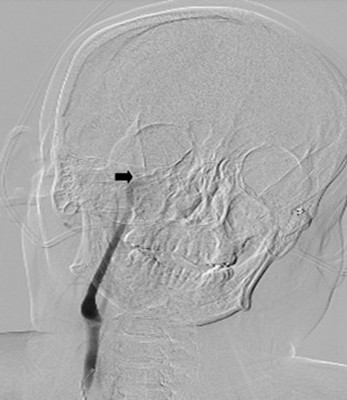

图1:造影见右侧颈内动脉成残端

考虑患者年轻,一般情况可,建议可急诊行介入下脑动脉内取栓手术。经患者家属同意后,急诊行全脑血管造影,造影见患者右侧颈内动脉颅内段于眼动脉处成残端,右侧大脑中动脉和右侧大脑前动脉均未见显影,即患者是右侧大脑半球全部缺血,病情危重,命悬一线,取栓需要分秒必争。最终经过约2小时的急迫手术,我神经内科介入小组成功从患者颅内血管闭塞处取出多枚栓子,总共约2CM长,实现颅内血管完全再通(见图1-3)。